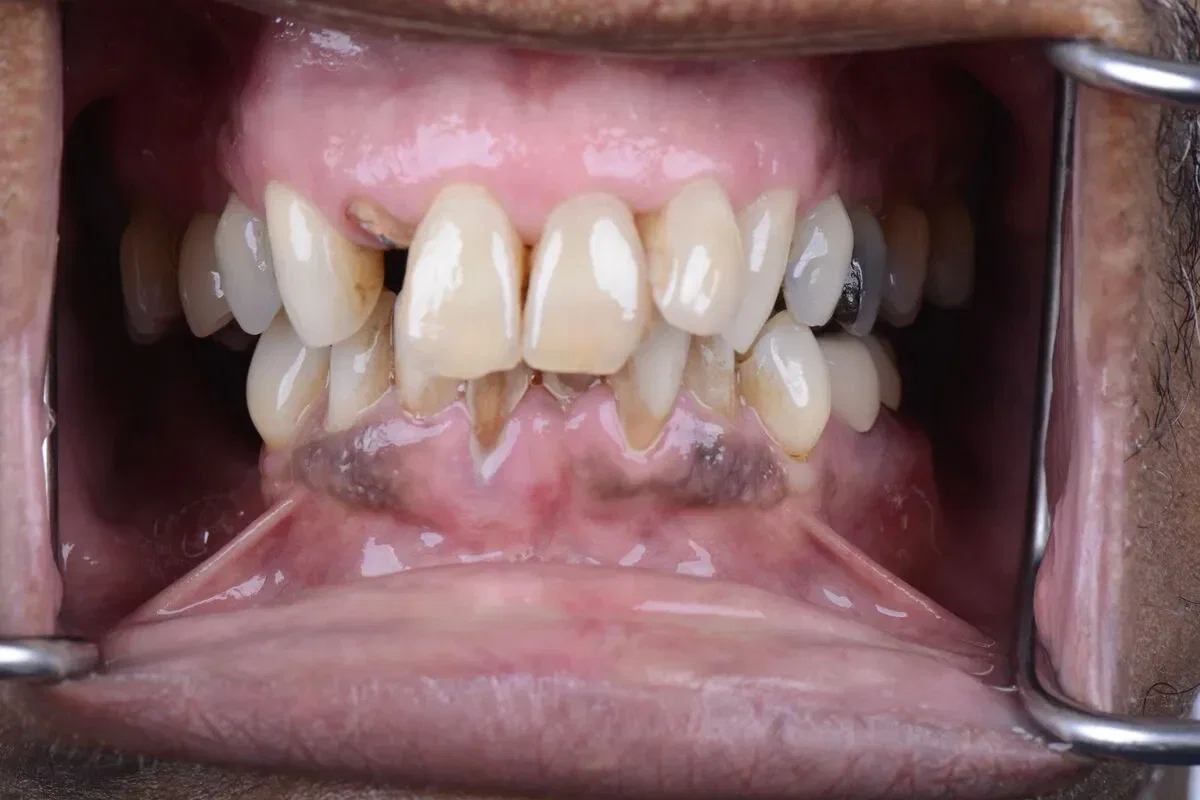

Real Smile Transformations

See the life-changing results from real patients who chose Fusion Dental Implants.